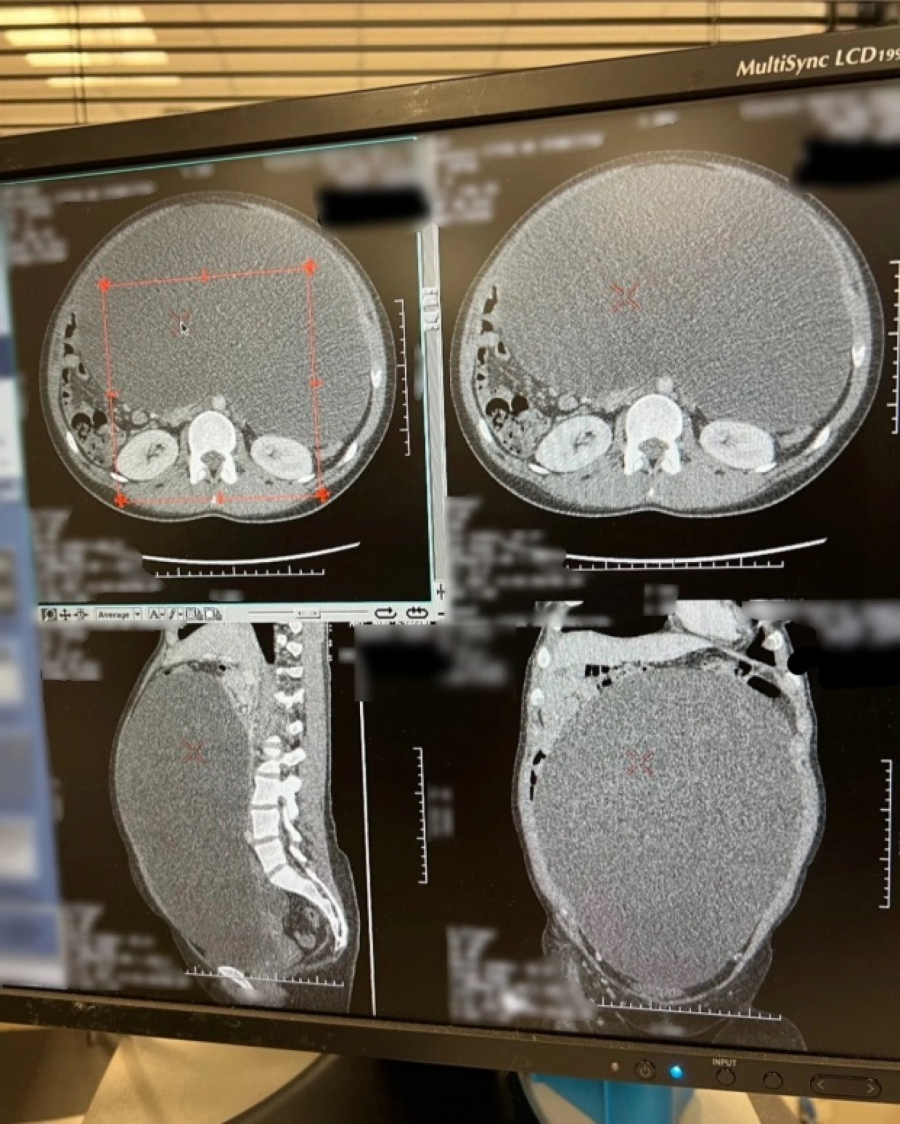

Nakon nekoliko meseci, kako je stomak sve više rastao, samoinicijativno je otišla na ultrazvuk. Otkrila je da ima cistu ispunjenu tečnošću na desnom jajniku. Da stvar bude gora, bila je teška oko devet kilograma. Nakon operacije koja joj je spasila život, iz želuca je ispušteno deset litara tečnosti, a desni jajnik je uklonjen.